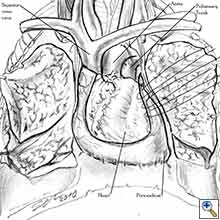

Pericardial reconstruction after anterior mediastinal tumor resection

Some pericardial defects resulting after partial pericardiectomy for invasive anterior mediastinal masses need pericardial reconstruction (Figures 4a-c). This is not the case for small pericardial defects, but large and lateral defects require reconstruction, especially if a lung resection has been performed. In the case of pericardiectomy with pneumonectomy, the postpneumonectomy space plays an important role in the pathogenesis of cardiac herniation. En bloc resection of a mediastinal tumor, the pericardium and the lung increases the risk of herniation in a similar fashion. In the absence of a lung resection, lung atelectasis can also increase this risk. Following complex resections requiring vascular resection followed by reconstruction, the reconstruction can stabilise the vascular prosthesis and prevent it from kinking (Figure 4c). Another potential advantage of pericardial reconstruction is that in the event of a re-do sternotomy, the risk of cardiac laceration is reduced because it prevents sternal-cardiac adhesions from forming [5]

Video 1 depicts a pericardial reconstruction with Marlex after a right completion pneumonectomy with pericardiectomy for lung adenocarcinoma (see also Figure 1). The technique of pericardial reconstruction after the resection of invasive mediastinal tumours is illustrated in Figures 8a-c). Video 2 depicts a pericardial reconstruction with Mersilene mesh after the resection of a malignant thymoma invading the anterior pericardium (see also Figure 4b). The technique of right pericardial reconstruction after extrapleural pneumonectomy is illustrated in Figures 9a and 9b). Video 3 depicts a pericardial reconstruction using Gore-Tex Dual Mesh after a left extrapleural pneumonectomy (see also Figure 3). Care must be taken to prevent constriction (Figure 10).